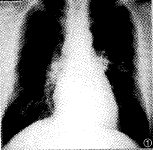

囊状PAVMs通常具有典型X线平片征象,表现为孤立或多发的类圆形阴影,阴影直径大小不等 ,密度均匀,边缘清晰,或有浅分叶;扩张增粗的供血动脉及引流静脉连于阴影,供血动脉 与肺门相连;该阴影一般不增大或仅缓慢增大。根据上述特点,结合临床资料多数囊状PAVM s可作出明确诊断(图1)。不典型者平片诊断有一定困难,例如本组2例复杂型多支供血囊状肺动静脉瘘,平片表现为大片致密影,很难根据X线平片作出正确诊断(图3)。弥漫型肺小动静脉瘘,多缺乏典型X线平片 征象,可表现为肺叶或肺段分布斑点状阴影(图5),也可表现为肺纹理增强、扭曲(图8),有 的病例平片无阳性所见。因此,弥漫型肺小动静脉瘘,X线平片诊断困难。

图1、2 X线平片示左肺舌叶类圆形阴影,造影证实为单发囊状肺动静脉瘘